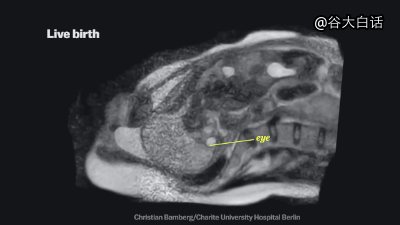

#爱你爱到骨头里#【MRI下诡异而奇妙的人体】这是一段用核磁共振成像技术制作的动态短片,将人类喝水、亲嘴、嘿咻、拉翔、生娃、说中文、说德文等日常活动展现得毫纤毕现、一览无遗。doge微猎奇,微暴,慎点。